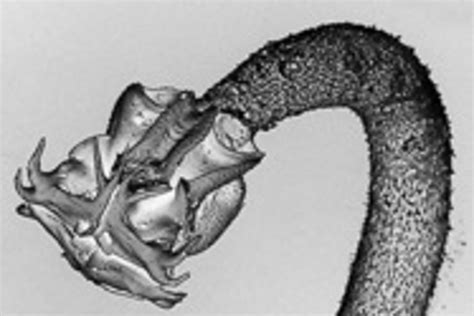

Tapeworms belong to the class Cestoda and are characterized by their flat, segmented bodies. These segments, known as proglottids, contain both male and female reproductive organs. Tapeworms can grow to considerable lengths, with some species reaching up to 30 feet in length. They live in the intestines of their hosts, where they absorb nutrients from the digested food, often leading to malnutrition in the host.

Larvae Learning about the development stages and intermediate hosts.

Adult Worms Identifying the structure and behavior of adult tapeworms.